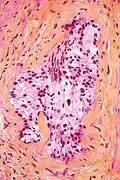

In pathology, perineural invasion, abbreviated PNI, is the invasion of cancer to the space surrounding a nerve. It is common in head and neck cancer, prostate cancer and colorectal cancer.

Unlike perineural spread (PNS), which is defined as gross tumor spread along a larger, typically named nerve that is at least partially distinct from the main tumor mass and can be seen on imaging studies, PNI is defined as tumor cells infiltrating small, unnamed nerves that can only be seen microscopically but not radiologically and are often confined to the main tumor mass. The transition from PNI to PNS is not precisely defined, but PNS is detectable on MRI and may have clinical manifestations that correlate with the affected nerve.[1]

Micrograph demonstrating perineural invasion. HPS stain.